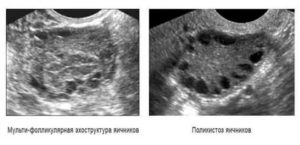

При мультифолликулярных яичниках на аппарате УЗИ наблюдаются:

- нормальный объем яичников;

- фолликулов всегда больше 7-8, объем каждого 4–10 мм3.

Учитывая эту особенность, специалисты, рассказывая про мультифолликулярные яичники, что это за нарушение, сравнивают его с одним из ультразвуковых симптомов, вариантом нормы. Однако, учитывая возможность наличия нечеткой клинической картины при поликистозе яичников, врачи всегда проводят дифференциальную диагностику, если у женщины обнаруживается мультифолликулярность этих органов.